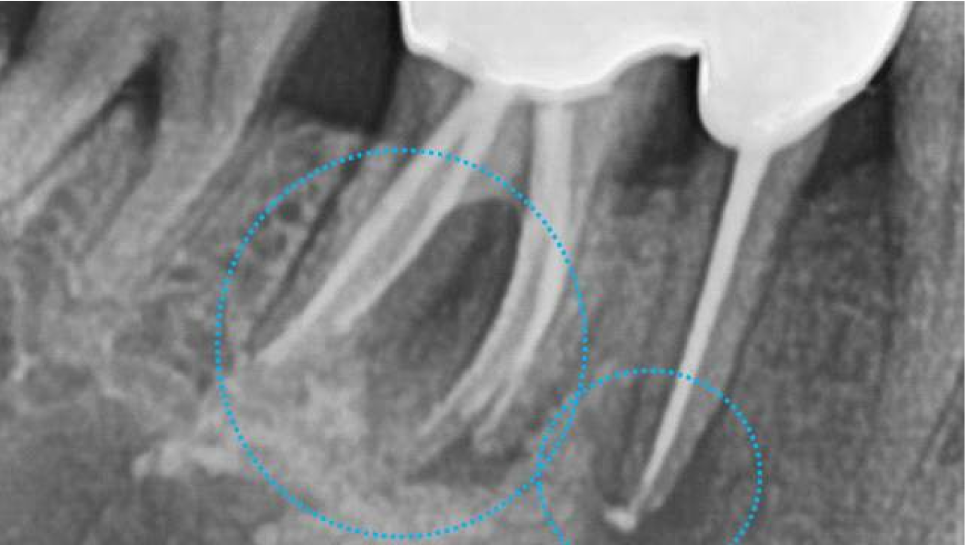

다음 오른쪽 아래 어금니의 3차원 CT 사진입니다.

보시면 까맣게 뼈가 녹아 있는 상태를 볼 수 있습니다.

치아 뿌리를 잡아주는 치조골이라는 뼈가

계속 염증으로 인하여 녹고 있는 상태입니다.

염증을 깨끗하게 제거하고

뼈이식을 같이 하기로 결정했습니다.

역시, 인접치 관계를 고려해서,

가장 이상적이고 안전한 위치를 찾아

적정한 두께와 길이의 임플란트를 선택했습니다.

아래 어금니 같은 경우에는

신경이 손상되지 않도록 수술하는 것이 가장 중요합니다.

어금니 뿌리 아래부분에 ‘하치조신경’이라는 신경이 지나가는데

손상되면 안면마비가 올 수 있기 때문에 항상 조심해야 합니다.

3차원 CT사진에서 빨간색으로 표시해놓은 신경관을

피할 수 있도록 CT를 분석하고

이에 맞는 직경과 길이의 임플란트를 선택하여

수술을 시작하였습니다.